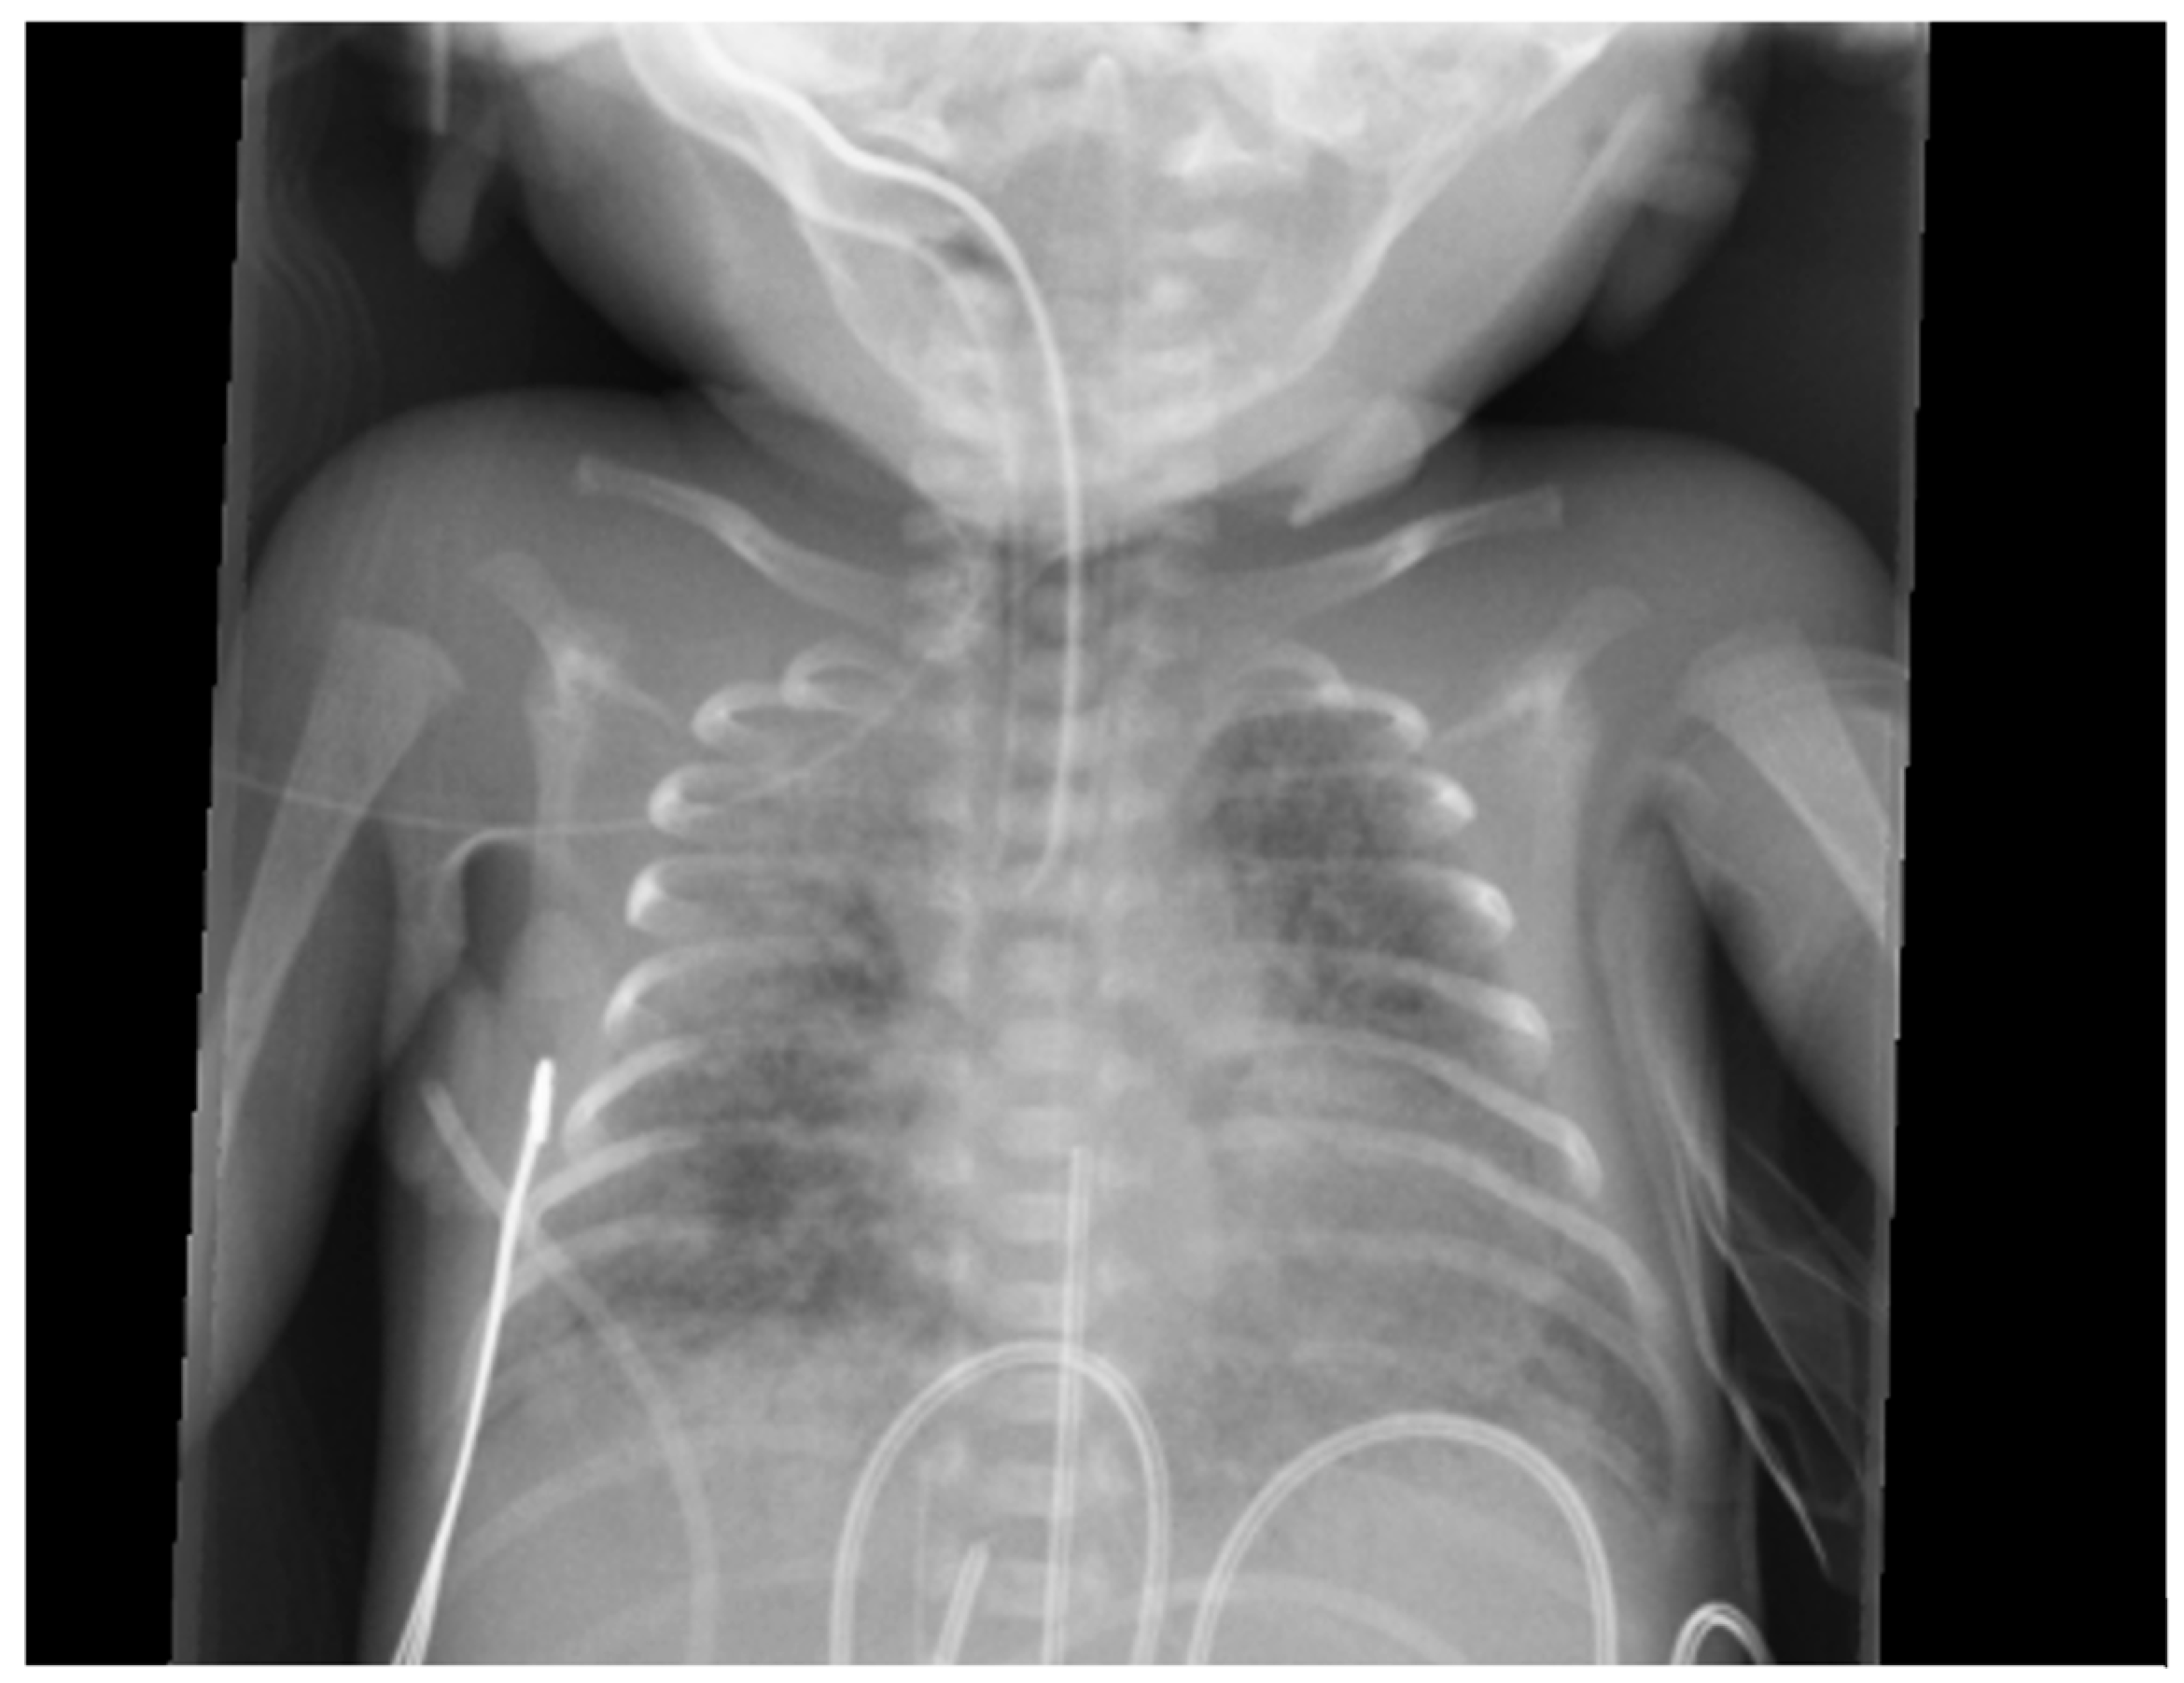

6.3. Radiological Diagnosis